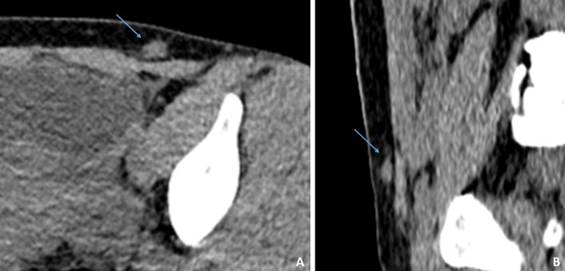

Se le realizó una ecografía en la que la lesión parecía depender de la pared. También se realizó tomografía axial computarizada que informó lesión con afectación de grasa subcutánea y del músculo recto anterior izquierdo, de bordes irregulares, de 5 cm x 3 cm x 3 cm, con densidades basales de partes blandas y con realce positivo. Ante los hallazgos se planteó posible diagnóstico de endometriosis, sin poder descartar tumor de otro tipo (Figura 2).

Se decidió realizar hernioplastia tipo Rives y exéresis de tumoración de pared que se remitió a anatomía patológica para su estudio histopatológico, el cual reportó nódulo constituido por tejido fibroso entremezclado con estroma y glándulas de tipo endometrial.